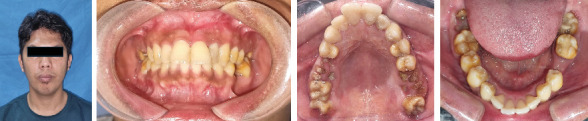

Introduction: Radicular cysts are the most common type of inflammatory cyst of the jaw. Management of radicular cysts may include cyst enucleation with apical resection. Spontaneous bone healing after cyst enucleation has been reported to occur in 73.5% of cases after 12 months. Residual cavity size was reduced 12.34% after 6 months, 43.46% after 12 months, and 81.30% after 24 months after surgery. This case report presents the use of platelet-rich fibrin and carbonate hydroxyapatite in the management of a radicular cyst for bone regeneration. This combination has not been previously reported. Case Report: A 31-year-old male complained of swelling of the anterior maxilla for 1.5 years. The patient had a history of pain and previous dental restorations. A biopsy confirmed the diagnosis of a radicular cyst. The cyst in the tooth region 21-23 was treated with enucleation of the cyst and apical resection. We used PRF with CHA on the cyst defect to enhance healing and bone regeneration. CBCT showed that bone density increased, and the size defect area buccal-palatal expansion reduced 54.4%, and mesial-distal expansion reduced 35.7% after 6 months of surgery. Conclusion: PRF and CHA may be used to accelerate bone regeneration in radicular cyst management.